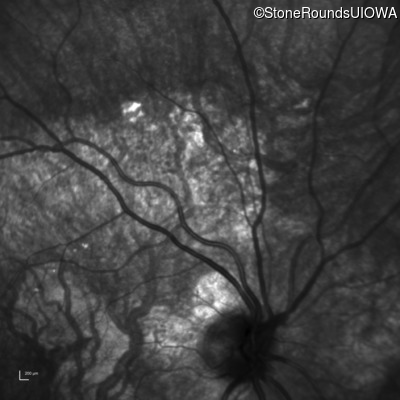

Infrared Fundus Photograph - Left - 20/30 +1 sc

Exemplar